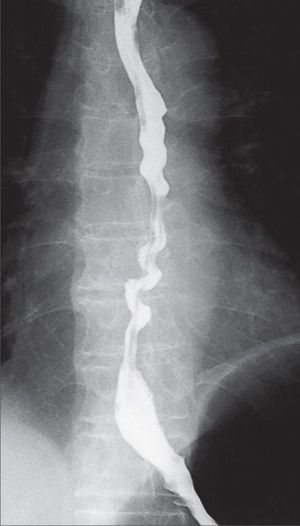

What's your diagnosis??and what's the treatment of it??

Barium contrast esophagus

Most likely it is DES but one shuld perform manometry studies to confirm the diagnosis

Diffused esophageal spasm. The treatment is nitroglycerin group drugs,CCB and butoliis

Diffuse Esophageal Spasm•••Calcium Channel Blockers